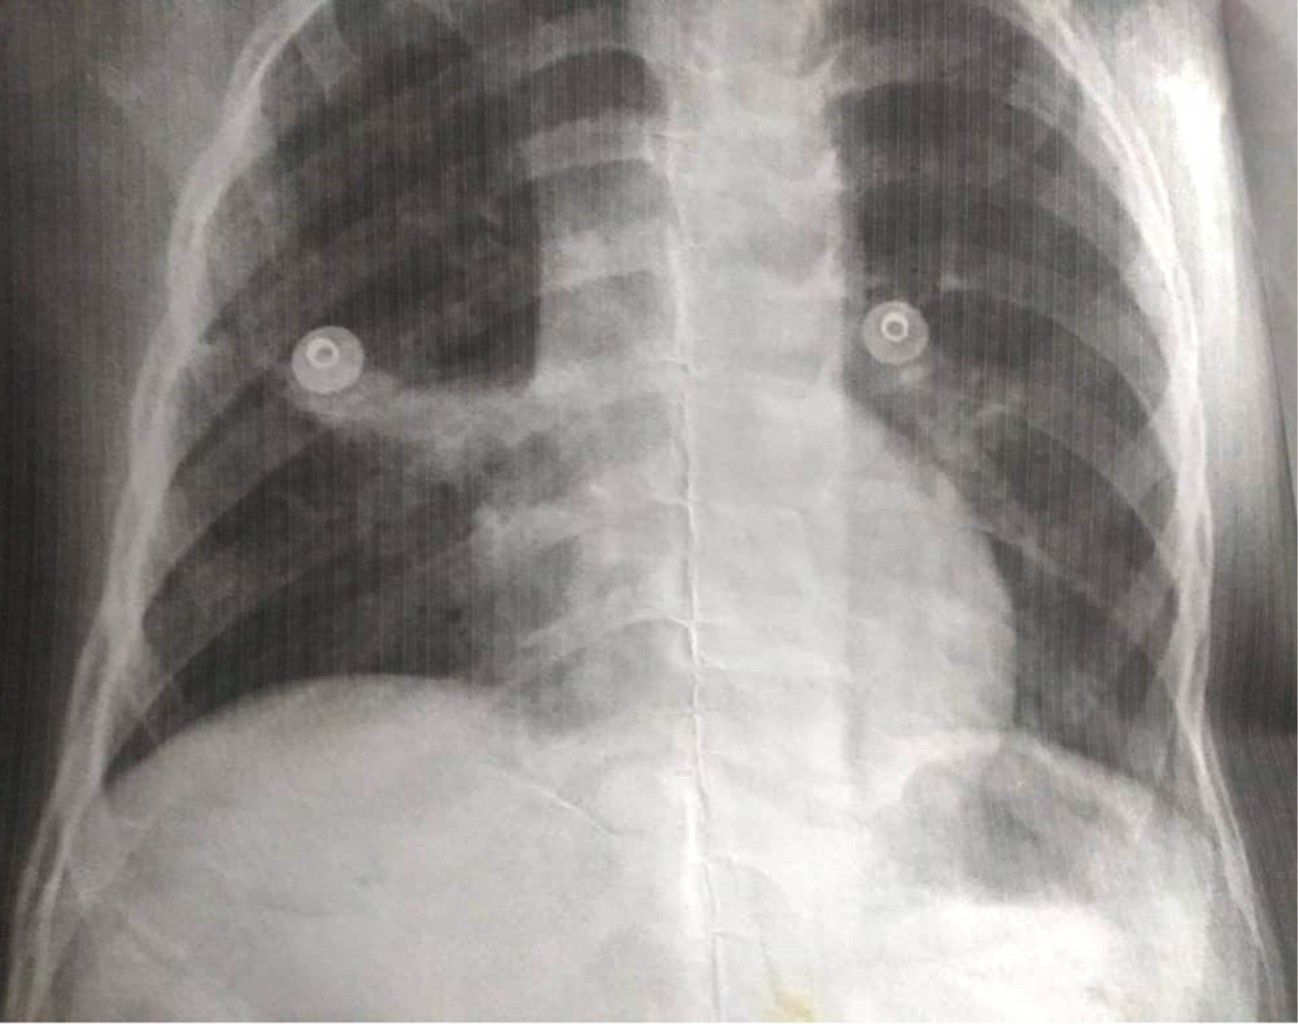

Estudios: difusión de monóxido de carbono (DLCO) 7.5 mL/min/mmHg (valor predicho 10.2), espirometría posbroncodilatador con una respuesta en volumen espiratorio forzado en el primer segundo (FEV1) del 16% y de más de 200 mL. La radiografía de tórax muestra un patrón atelectásico (Figura 1). Serie esofagogastroduodenal (SEGD) con presencia de reflujo grado III; en la angiotomografía de tórax (angio-TC) se observa una subclavia derecha aberrante (Figura 2), lo mismo que en la aorta descendente, también un vaso aberrante (Figuras 3 y 4).

Por otra parte, las técnicas de imagen son pruebas complementarias que confirmarán el diagnóstico. La radiografía de tórax puede proporcionar información sobre el desplazamiento del arco aórtico o la tráquea, la presencia de una estenosis traqueal, así como infiltraciones pulmonares, distelectasias o atelectasias como signos de compresión de las vías respiratorias.9 El esofagograma muestra la indentación esofágica; sin embargo, la información anatómica obtenida no es lo suficientemente precisa para el tratamiento terapéutico, por lo que se requieren imágenes transversales como la tomografía computarizada (TC) o la resonancia magnética (RM). Se pueden usar métodos de posprocesamiento para generar datos 3D, tanto de la TC como de la RM, dando una vista detallada de la morfología vascular.10 En cuanto a los estudios de radiología la SEGD no reveló identaciones esofágicas, sólo la presencia del reflujo severo; tampoco la tele de tórax mostró imágenes radiológicas sugerentes de las malformaciones, por lo que no fueron concluyentes para el diagnóstico. Por lo tanto, la TC de tórax y la angiotomografía son los estudios de elección para el diagnóstico de los anillos vasculares y de las malformaciones pulmonares como lo es el secuestro pulmonar intralobar o extralobar, la otra patología agregada en nuestro paciente.